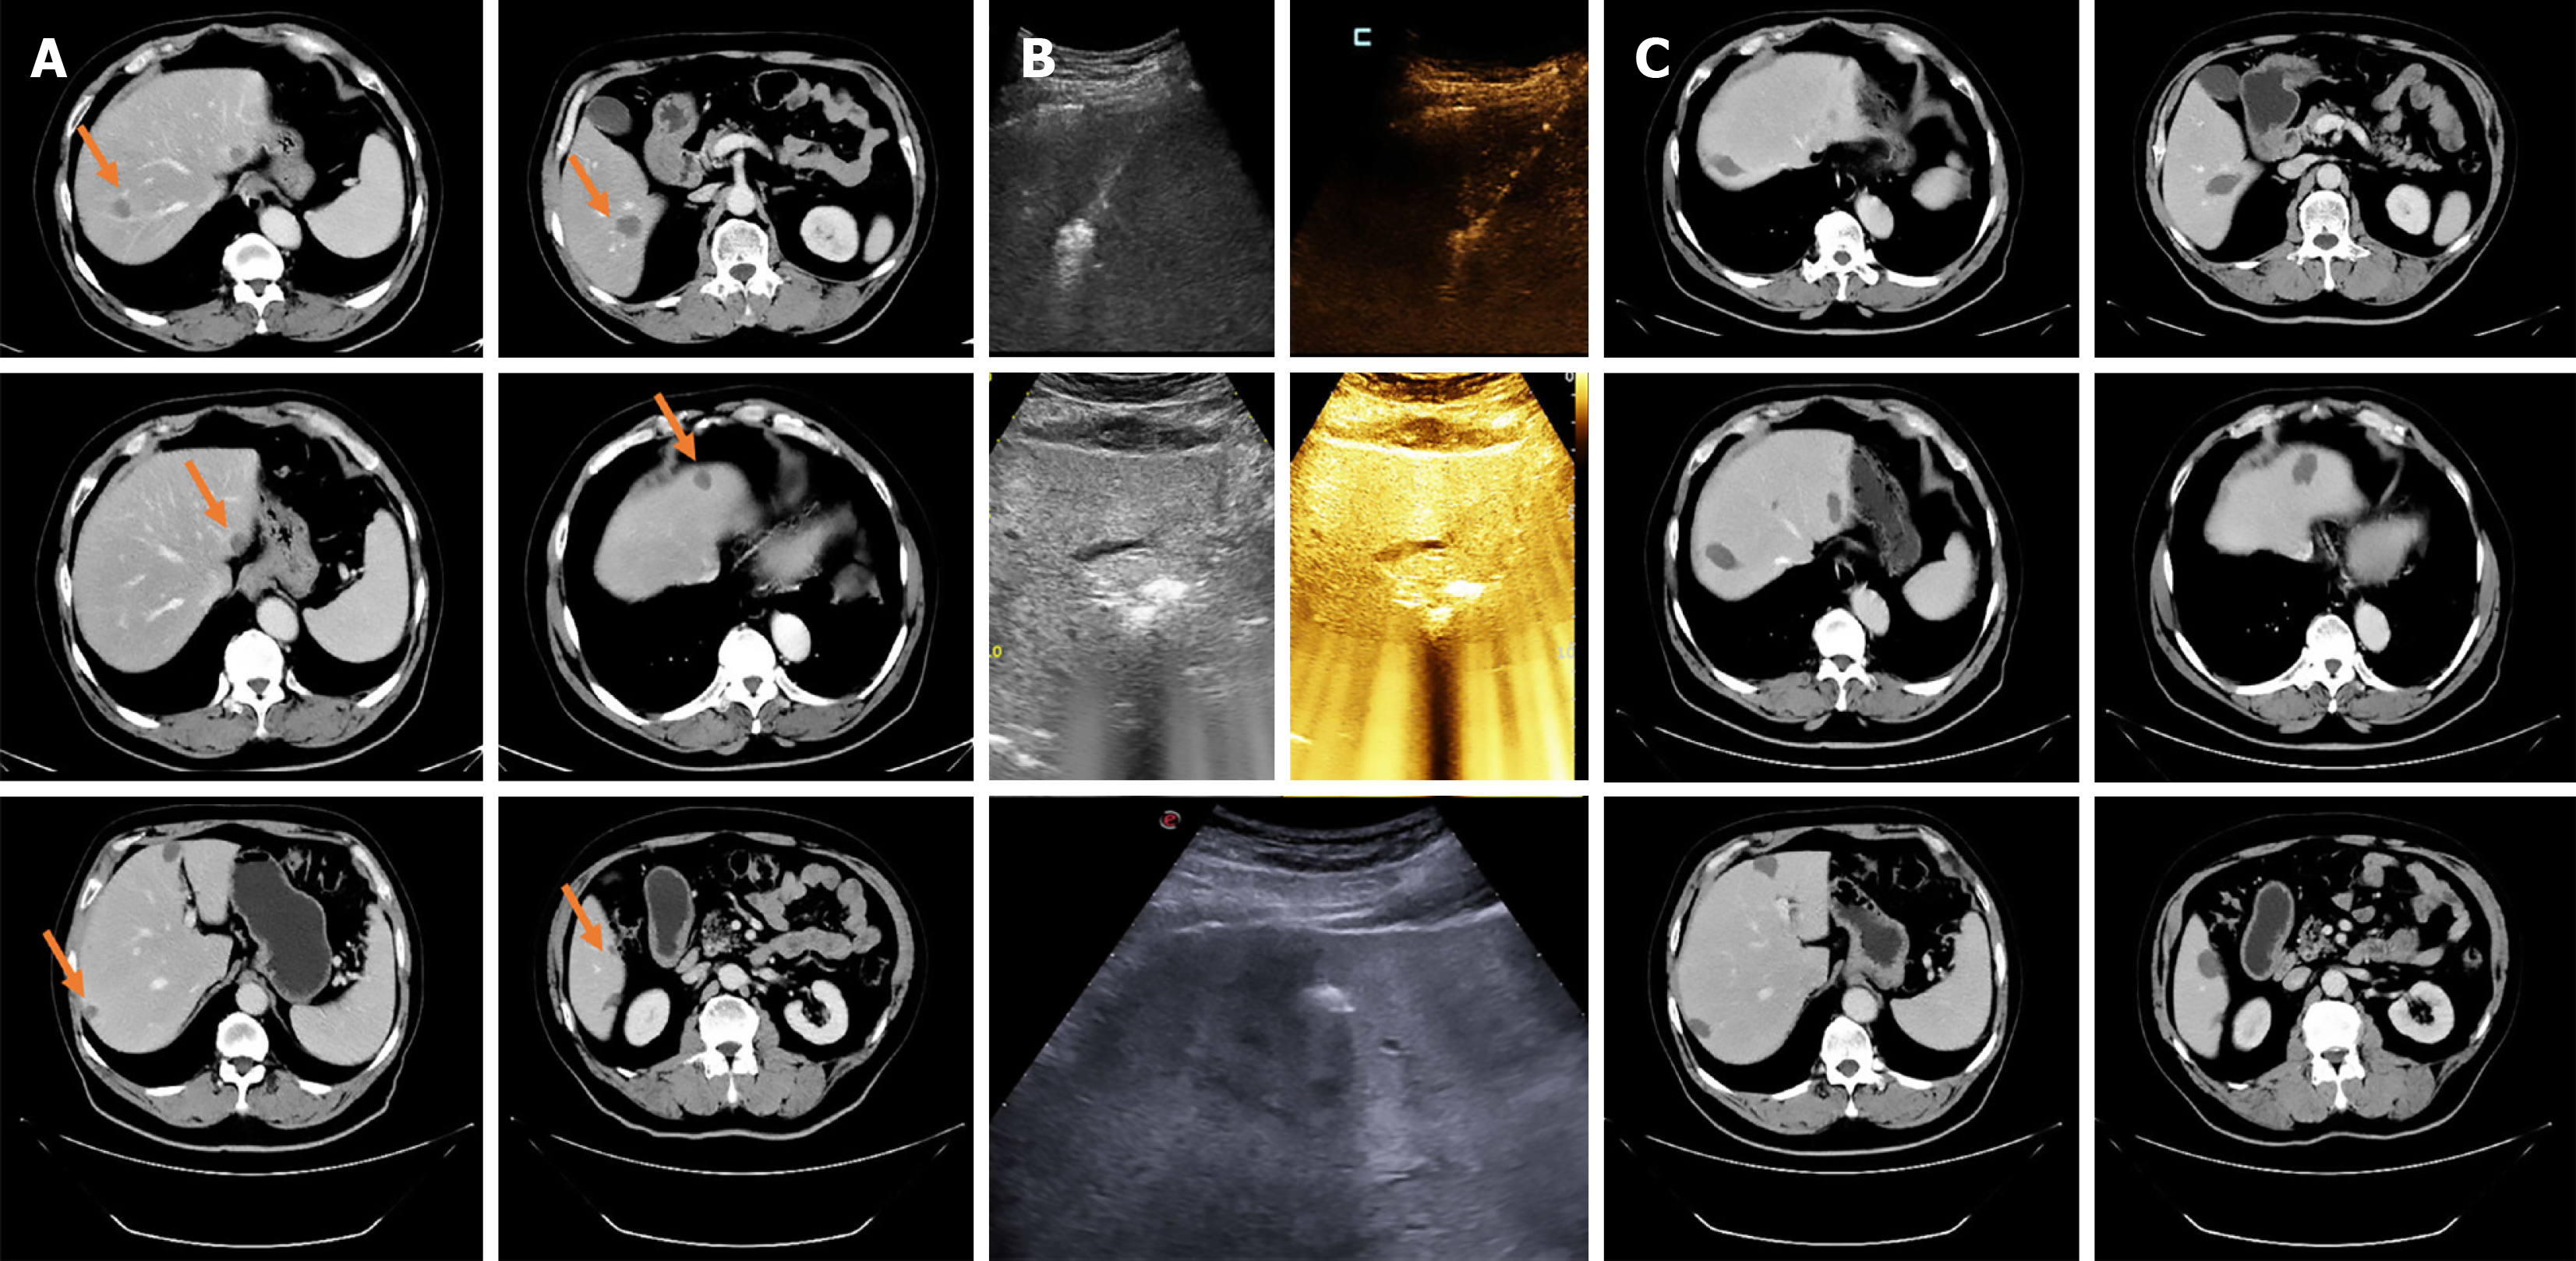

Figure 3 Repeat ablation: A 58-year-old male patient with an initial total of 9 colorectal liver metastases completed ablation in 3 sessions.

Within 3 months, 2, 3, and 4 lesions were ablated separately. A: Pre-ablation imaging (orange arrows point to the target lesion); B: Intraoperative contrast-enhanced ultrasound/ultrasound; C: Post-ablation imaging.